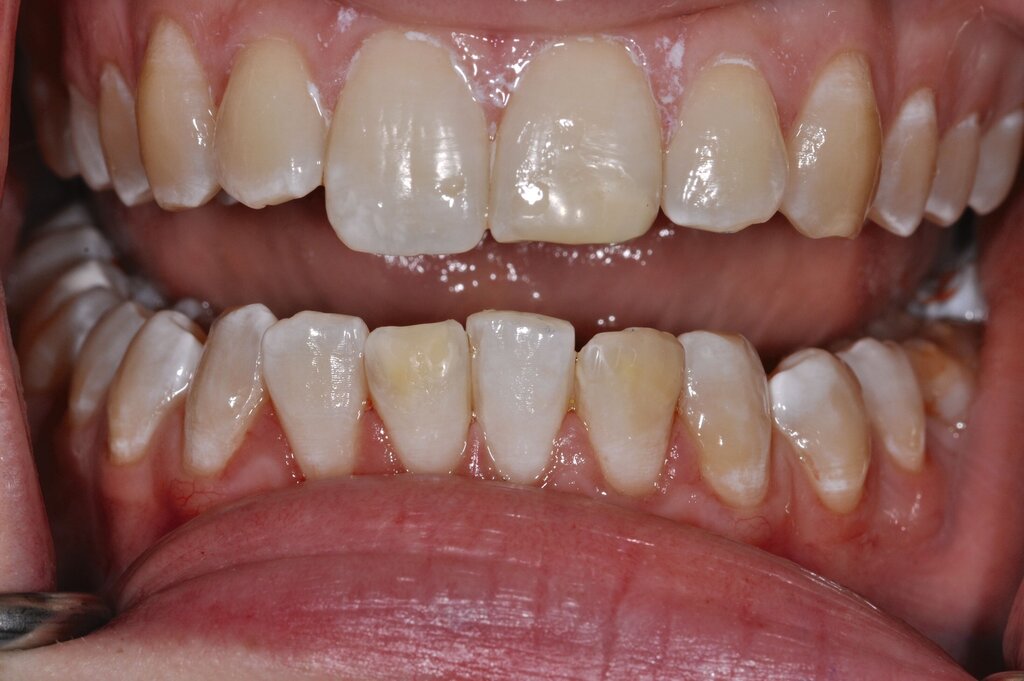

Diese Klassifikation dient als Grundlage für die Therapieempfehlungen. Deutlich wird, dass aufgrund der Symptomatik die Therapie der Zähne höchst unterschiedlich ausfällt. Dass etwa eine Opazität ohne Überempfindlichkeit (Index 1, Abbildung 1) ein anderes therapeutisches Vorgehen erfordert als ein Zahn mit nahezu komplettem Einbruch der Zahnoberfläche und mit Hypersensitivität (Index 4, Abbildung 2), ist offensichtlich.

Für die zahnärztliche Praxis gibt die Einteilung eine Orientierung darüber, welche Behandlungsmaßnahmen erforderlich sind beziehungsweise eingesetzt werden können. Je nach Schweregrad wird dabei zwischen nichtinvasiven und invasiven Maßnahmen sowie einer kurzzeitigen oder längerfristigen, restaurativen Therapie unterschieden. Bei der Überarbeitung des Konzepts wurde zudem zwischen Front- und Seitenzähnen differenziert (Abbildung 3) [Bekes et al., 2023; Steffen et al., 2017].

Die Therapie C hat das Ziel, MIH-Zähne vorübergehend zu versorgen, bis der vollständige Durchbruch der Zähne eine adhäsive Restauration ermöglicht, um die hypersensiblen Zähne zu desensibilisieren oder/und die Mitarbeit für die weitere Behandlung aufzubauen. Vor dem Hintergrund des erhöhten Kariesrisikos dieser Zähne (Abbildung 2) muss durch die Maßnahmen eine Kariesprogression vermieden werden.